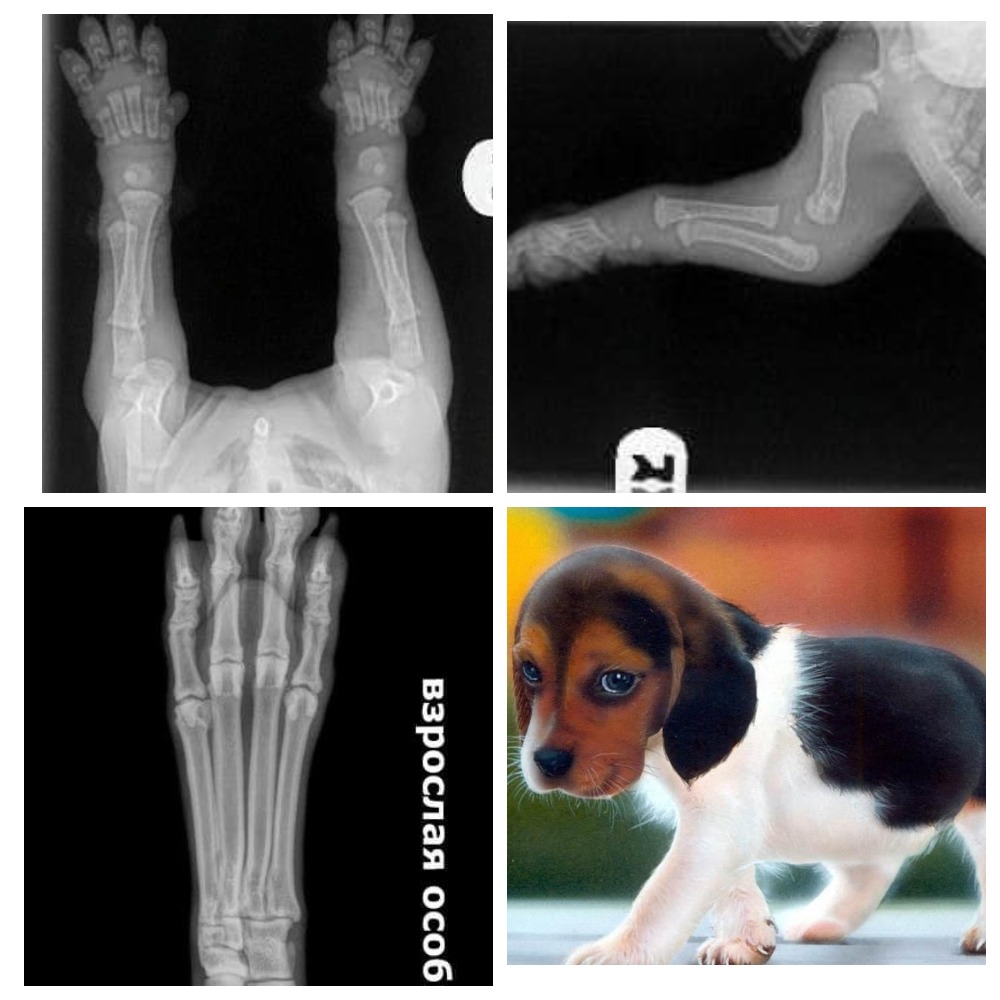

Когда вы получаете своих щенков в возрасте 8/10 недель, пожалуйста, помните об этих фотках. Видите их кости далеко друг от друга и даже нет намёка на соприкосновение. Вы заметили что все щенки, любой породы с большими гибкими лапками и шаткими движениями, их суставы полностью состоят из мышц, сухожилий, связок, покрытые сверху кожным покровом. Кости не могут плотно прилегать друг к другу пока не имеют настоящего гнезда - т.е. сформированного сустава. И чтоб защитить кости щенка от деформации Природа сделала так, что щенки много бездельничают и спят.

Каждый большой в длину или высоту прыжок или активные игры или подпрыгивающий бег вызывает удары между костями. Игры или тренировки в разумных пределах это не проблематично и является нормальным износом суставов для любого животного, но когда вы выполняете их чрезмерно или не ограничиваете щенков в упражнениях, вы не даете им возможности нормально расти.

Нужно понимать, что когда вы позволяете щенку прыгать вверх и вниз или бежать по ступенькам, или прыгать с кровати, или берёте его на длительные изнурительные прогулки / пробежки / походы, вы можете повредить эти формирующиеся суставы. Когда вы позволяете щенку скользить по плитке или ламинату или линолеуму, вы опять же можете допустить повреждение сустава.

Достаточно одного маломальского нарушения при формировании сустава и Вы можете изменить их за один раз на всю жизнь. Помните, что хорошо сложенное тело - это то, что происходит не только от отличного кормления и содержания, но и от правильного воспитания.